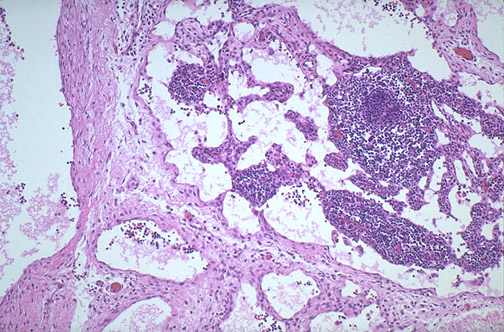

| Here is the microscopic appearance of the lymphangioma at medium power, with large lymphatic spaces lined by a thin endothelium. The adjacent stroma has lymphoid nodules. Lymphangiomas in the pediatric age range tend to involve head, neck, and chest. |